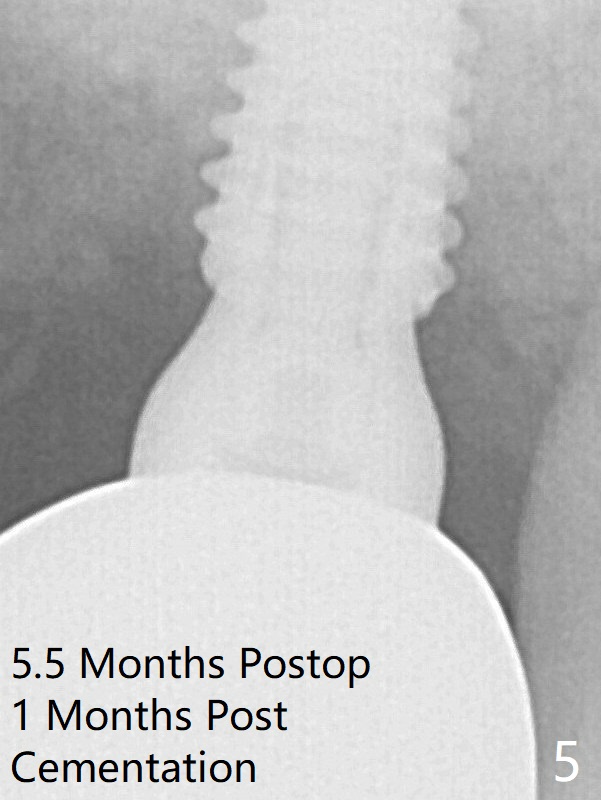

Sinus lift is accomplished with RT3 and autogenous bone prior to placement of a 4.5x8.5 mm implant (Fig.3). Because of flapless surgery and tight and long gingiva, bone graft around the coronal end of the implant is intentionally not placed. A 5.5x5(4) mm abutment is immediately placed for an immediate provisional. The provisional dislodges 3.5 months postop (Fig.4); impression is taken. The patient reports hot sensitivity and pain after meal at the implant site (Fig.5). After removal of the implant crown/abutment, she feels better.